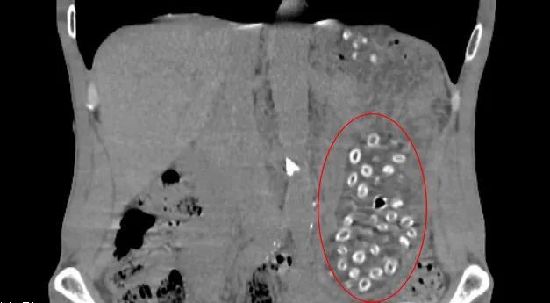

經(jīng)CT檢查后發(fā)現(xiàn)胃潴留,胃內(nèi)可見大量顆粒狀物體,密密麻麻,詢問得知王大伯近期大量食用楊梅且不吐核,以下影像中呈現(xiàn)的就是沒有消化的楊梅核。

入院后,消化內(nèi)鏡室醫(yī)生在胃鏡下實(shí)施“異物取出術(shù)”,通過異物網(wǎng)籃來回?fù)屏?00多次,取出100多顆楊梅核,目測胃里還有幾十顆。幸好發(fā)現(xiàn)的及時,不然后果不堪設(shè)想。